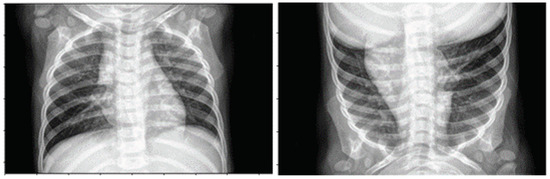

4.1. Data